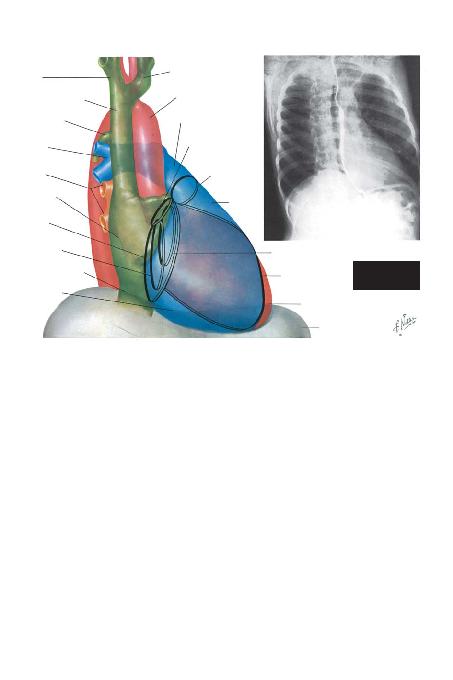

Frontal Görüntü (Sayfa 22). Ço¤u gö¤üs filmi fron-

tal (anteroposterior) projeksiyonda yap>ld>¤> için, kal-

bin bu görüntüsü genellikle de¤erlendirilir ve s>kl>kla

kalp hastal>klar>n>n varl>¤> hakk>nda ilk düflüncelerin

oluflmas>n> sa¤lar. Kural olarak bu görüntüde sol atri-

yum, sol ventrikül ve sa¤ atriyumun büyüdü¤ü durum-

lar tespit edilebilir. Her ne kadar bir s>n>r oluflturmasa

da, sa¤ ventrikül kardiyak konturda karakteristik de¤i-

fliklikler yaratabilir. En kolay tekrar edilebilen projeksi-

yon oldu¤u için, kalbin büyüklü¤ü genelde bu görün-

tü ile de¤erlendirilir.

BRAKVEN

SUPER

AZYGOS VEIN

SOL ATR

SA/ VENTR

SOL BRAK

AORTA

PULMONER TRUNK

M

SOL VENTR

D

SOL PULMONER

ARTER

AORTHALKASI

PULMONER KAPAK

HALKASI

SA/ VENTR(ÇIKIfi)

SULKUS

VENLER

ATRSULKUS

TRHALKASI

KALBANTERRADYOGRAMININ

YORUMLANMASI